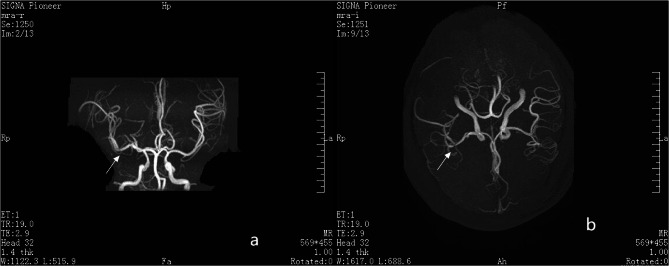

Case description: A pediatric patient presented with AIS involving the left limb, lasting 2.5 h. The stroke occurred during physical activity without loss of consciousness or seizures. Head magnetic resonance imaging (MRI) combined with clinical manifestations confirmed the diagnosis of acute cerebral infarction. Intravenous thrombolytic therapy using tenecteplase was initiated in the ultra-early phase of infarction. Subsequent cerebral angiography revealed occlusion of the superior trunk of the right middle cerebral artery. Three-dimensional rotational imaging identified multiple aneurysms at its bifurcation. A targeted intra-arterial injection of tirofiban (6 mL) was administered to stabilize plaque and enhance blood flow. The patient underwent 11 days of antiplatelet therapy and supportive care. At the 90-day postoperative follow-up, notable recovery of limb function was observed.